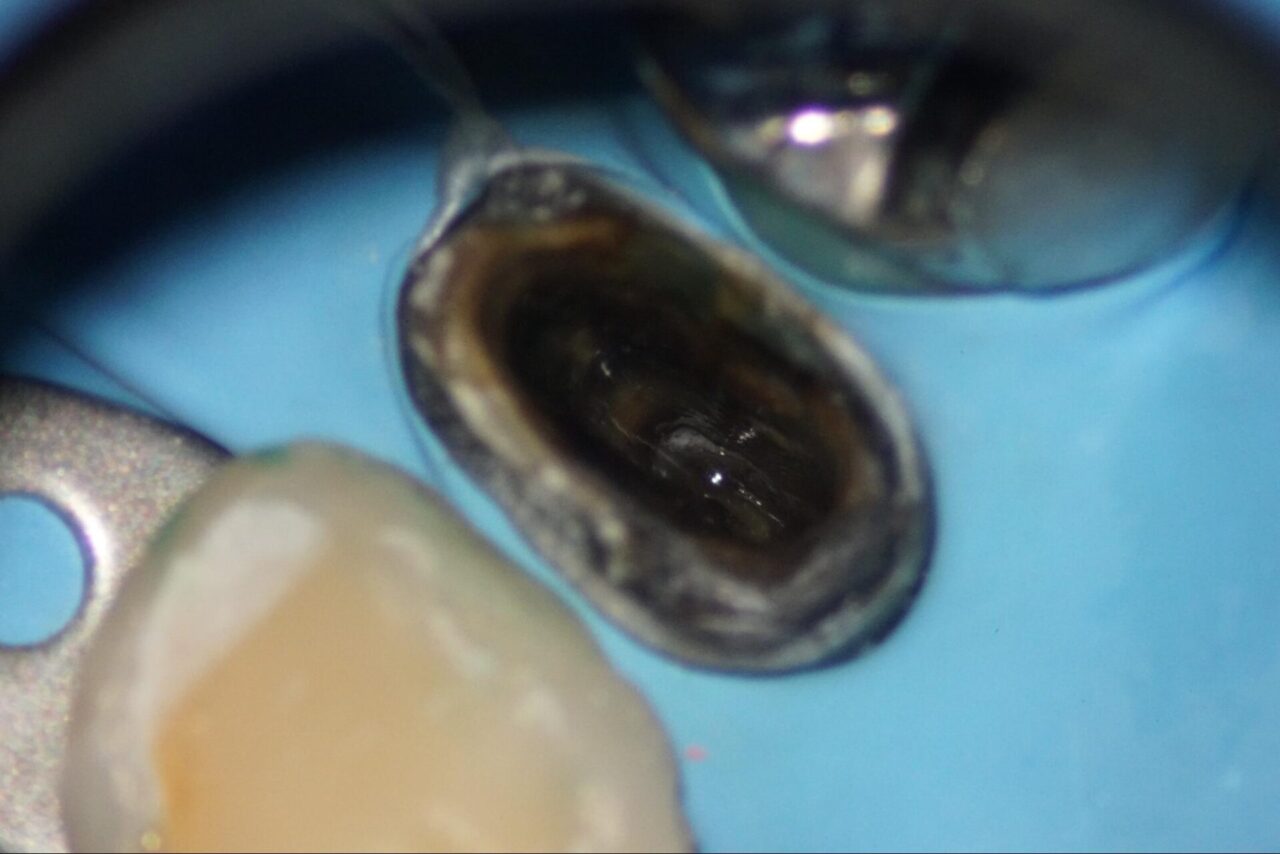

以前の先生が行った根管充填材も除去していきます。

根尖部の根管充填材も除去していきます。

根管充填材が除去できている事をレントゲンで確認して、根管洗浄を薬品やレーザーなどを用いて行います。

根管内を乾燥させるとクラックラインが確認できます。

標準的な診断基準であればこの時点で根管治療は終了になり、抜歯になります。

しかし吉松歯科医院では、私の過去の経験から接着して歯を残す事を行っています。